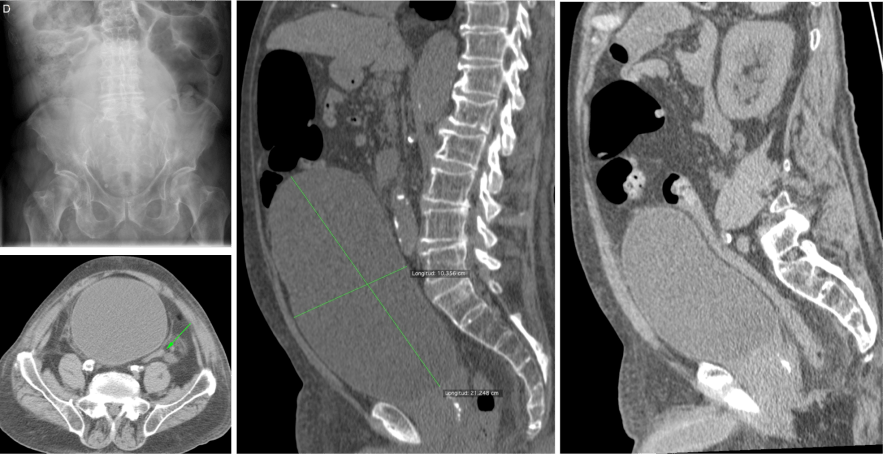

VÓVULOS.

Es una obstrucción en asa cerrada. Tambien nombraremos al vólvulo gástrico, que poduce una obstrucción alta.

En el vólvulo intestinal, los hallazgos en TC mostrarán una morfología “en grano de café”, dos tipos:

- De sigma: con vértice orientado hacia FII, morfología en “U invertida” y doble nivel hidroaéreo. No suele asociar dilatación de asas de delgado.

- De ciego: con vértice orientado hacia FID y único nivel hidroaéreo. Suele asociar dilatación de asas de delgado.